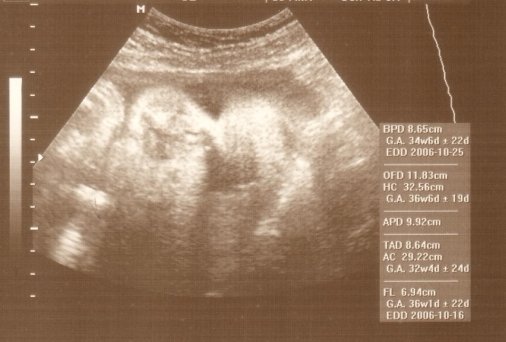

Szóval türelmesek leszünk, csak fájdogál a pocim, meg hát nyűgös vagyok, nem nagyon férek már a bőrömbe. Pocim hatalmasat nőtt 1 hét alatt, magam is megdöbbentem. Hízni viszont csak fél kilót híztam. Hát ennyi volt a dokinál.

5 kg-t híztam, az kb. pont a baba. Mert ugye kb. 3 kilót mondtak tegnap, hogy annyi már van, meg kb. 2 kiló a kellékek (magzatvíz, magzatburok, méhlepény). Hát nem így terveztem, meg közben idegesítettek is vele, hogy ez nem egészséges, de most már jól érzem magam tőle. Így nem viselte meg annyira a szervezetemet a terhesség.

Azért nagyon örülök, hogy a mi buksiméretünket kisebbnek mondják.